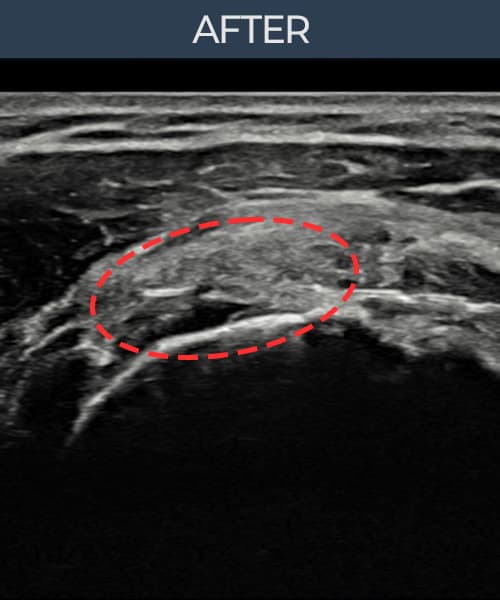

초음파로 보는 치료결과

실제 환자의 시술 전후 초음파 영상입니다.

수술 없이 이뤄낸 회복을 직접 확인하세요.

모든 초음파 영상은 실제 환자의 동의를 받아 게시하였습니다. 개인차가 있으며 동일한 결과를 보장하지 않습니다.